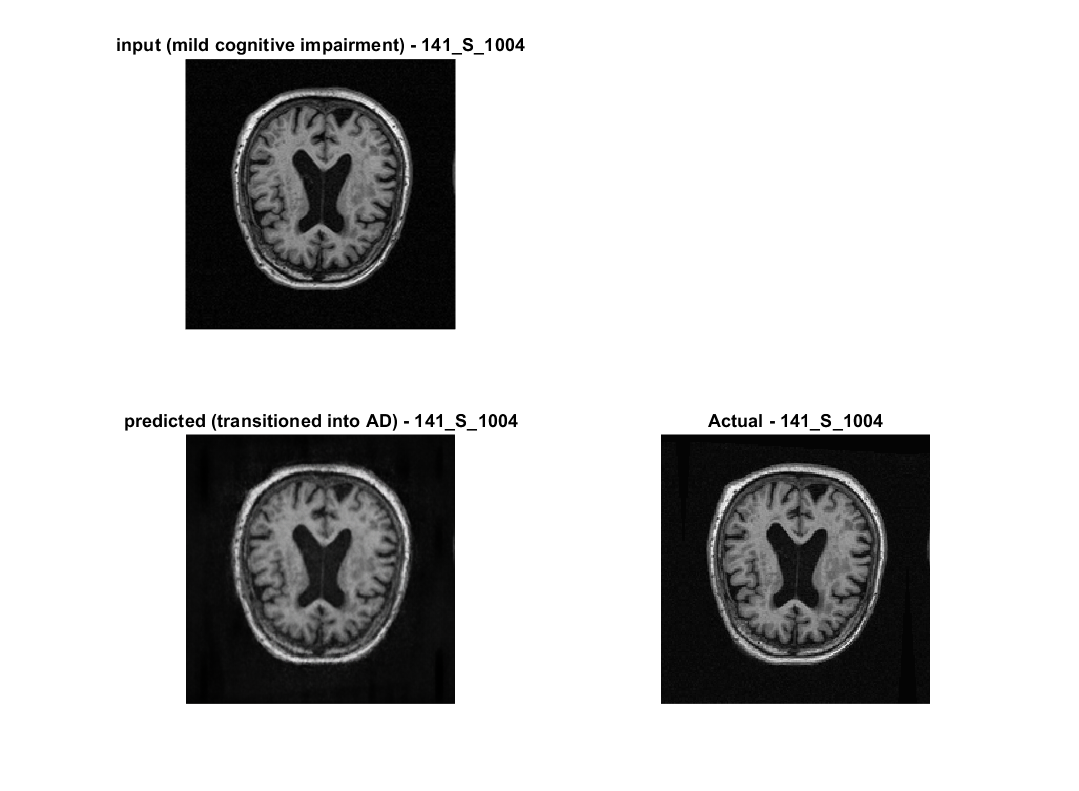

Once image registration is done, we can train and evaluate our models.